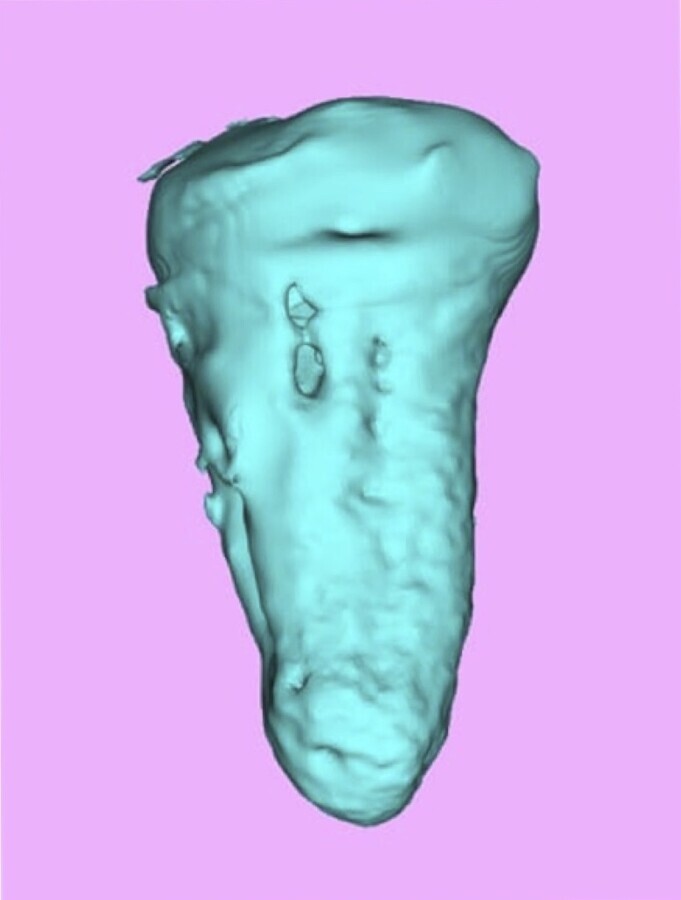

Figura 3. Prototipo rápido creado en computador del diente 37.